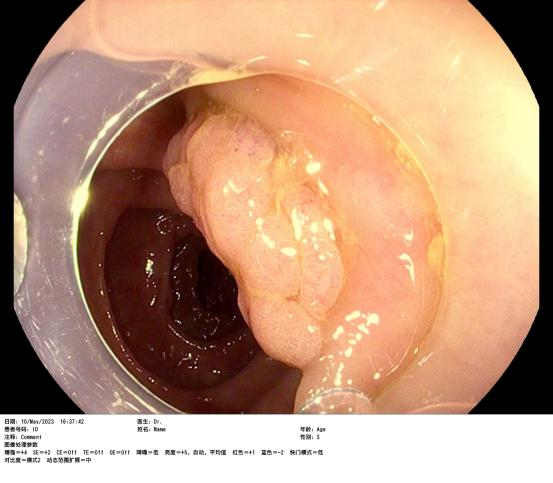

患者賴女士因下腹部疼痛不适半月,在惠州六院行腸鏡檢查時(shí)發(fā)現橫結腸腫物,腫物大小約2.8cmx2.0cm,表面(miàn)充血,于是入院完善采血、心電圖、胸片、全腹部增強CT等一系列檢查,增強CT結果提示腫物未見腸管外浸潤生長(cháng),經(jīng)評估該患者有手術指征,在與患者及家屬充分溝通後(hòu),由消化内科蘇連明副主任醫師爲患者行内鏡下結腸黏膜剝離術(ESD),手術非常順利,術後(hòu)病理及免疫組合明确診斷爲高級别上皮内瘤變——俗稱早期結腸癌。